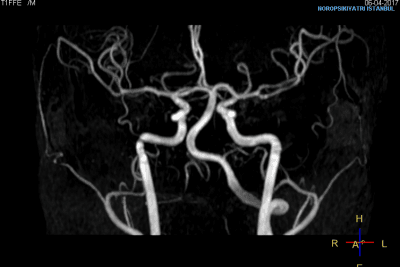

للتصوير أهمية كبيرة في تشخيص أمراض الدماغ وعلاجها ومتابعتها. يوفر الاستخدام الفعال لتكنولوجيا التصوير بالأشعة من حيث التشخيص التفريقي ومراقبة التغيرات التي تحدث أثناء عملية العلاج راحة للأطباء وفائدة كبيرة للمرضى. يعد استخدام تكنولوجيا التصوير بالأجهزة الأكثر تطوراً في أمراض الدماغ أحد الامتيازات المهمة لمؤسستنا.

في مجال الطب النفسي، نحن من أوائل المؤسسات في تركيا التي تطبق تقنيات التصوير بالرنين المغناطيسي المتقدم للدماغ...

مختبر تصوير الدماغ (علم الأعصاب)